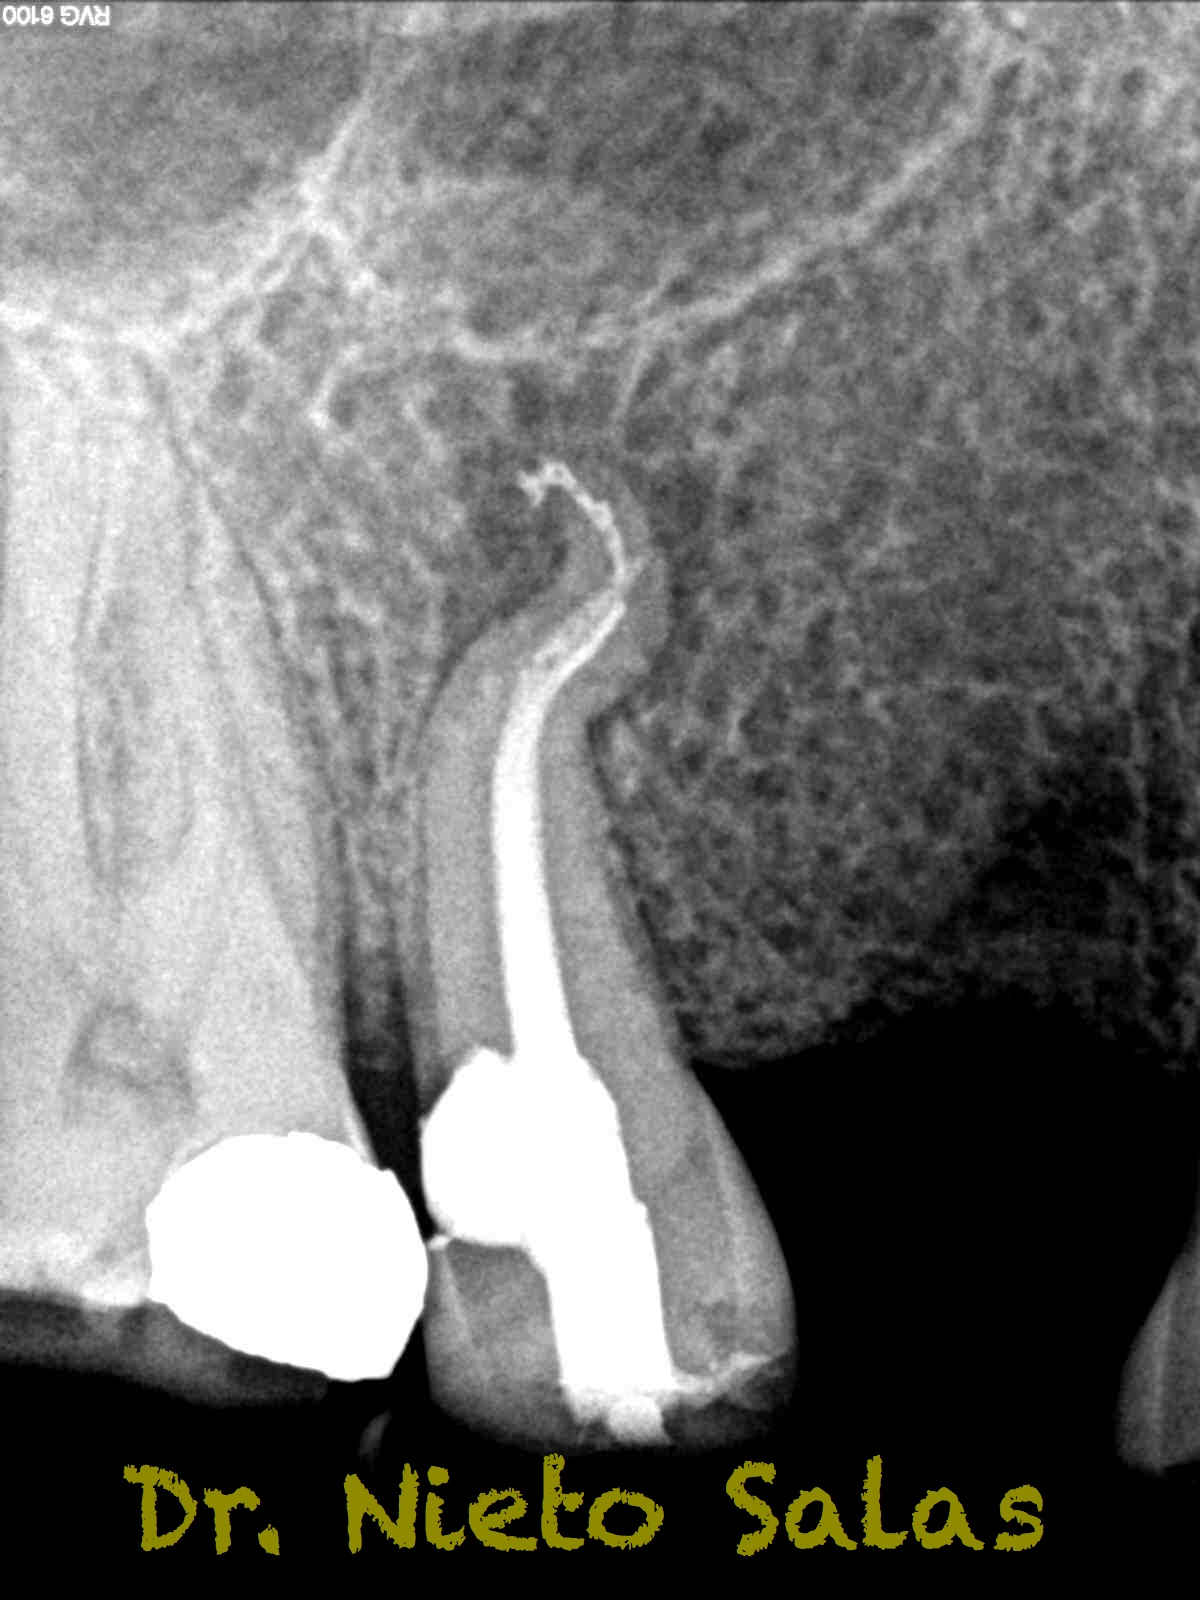

Conseguiríamos un sellado de esta manera en el caso A:

La obturación la haremos con el sistema de condensación vertical por ola continua de Buchanan.